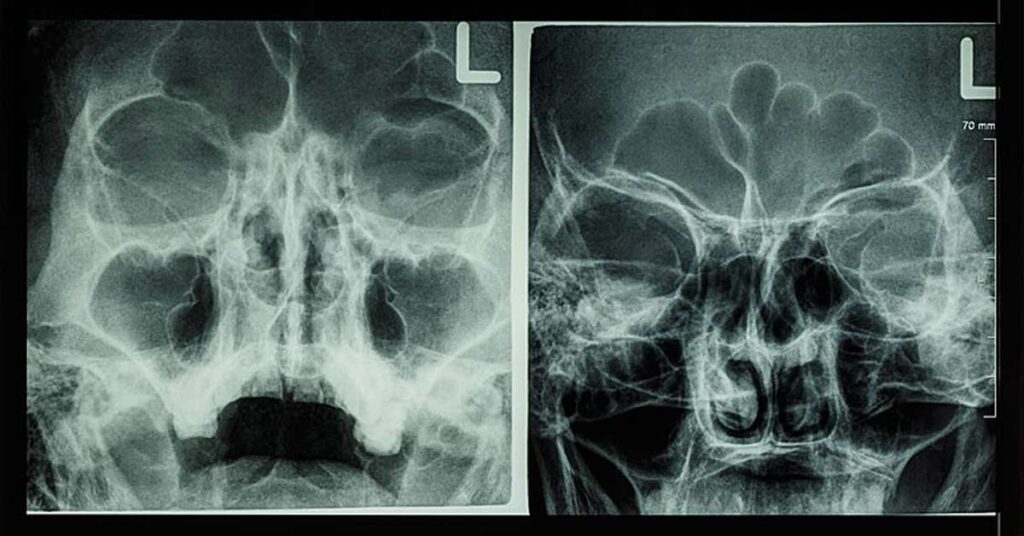

A tomografia computadorizada utiliza raios-X para criar imagens detalhadas do interior do corpo.

Durante o exame, o paciente passa por um grande dispositivo em forma de anel enquanto uma fonte de raios-X gira ao redor do seu corpo, capturando múltiplas imagens de diferentes ângulos.

Essas imagens são então processadas por um computador para formar uma visão detalhada em seções transversais dos tecidos e órgãos com muito mais precisão do que uma radiografia comum.

Esse método é particularmente útil para diagnosticar e acompanhar uma série de condições: fraturas ósseas, lesões internas, tumores, hemorragias, infecções, alterações nos órgãos internos, problemas em vasos sanguíneos e mais.